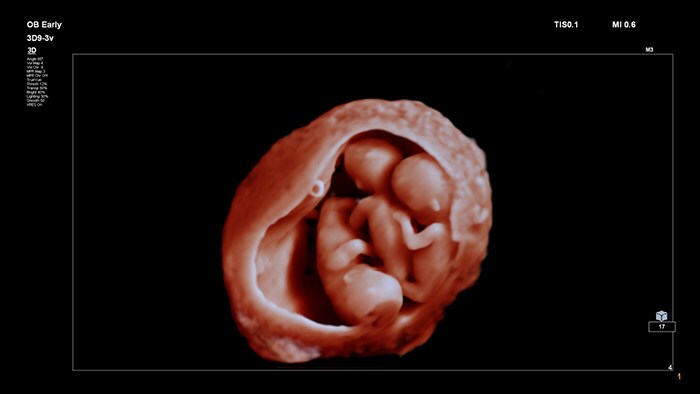

Благодаря технически совершенным, детально проработанным изображениям и возможности управлять гибким виртуальным источником света, интерфейс TrueVue дает возможность врачам и будущим мамам получать удивительно реалистичные изображения плода во время беременности.